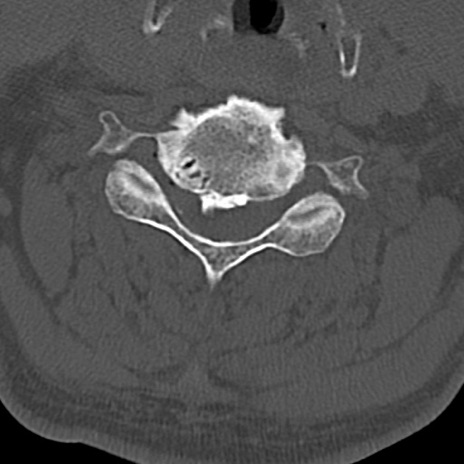

頚椎CT

横断像